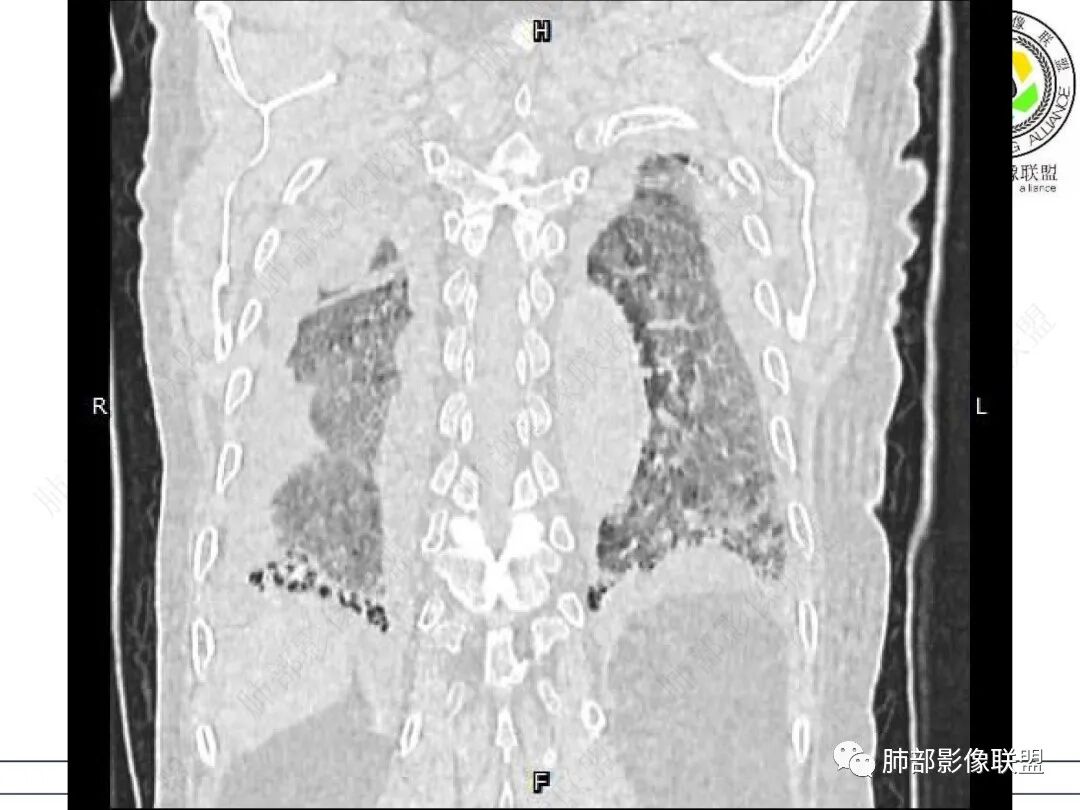

两肺叶后肋膈角区见多发蜂窝状结构破坏表现,双肺叶小叶间隔增厚,左肺上叶后段及舌段和右肺中叶胸膜炎性肉芽肿特点,双侧胸腔少量积液,有类风湿性关节炎治疗史,结缔组织相关性间质性肺病。

发热,有类风湿性关节炎、糖尿病基础病,长期口服激素及免疫抑制剂,双肺多发磨玻璃影及小叶间隔增厚,蜂窝影,支气管扩张考虑非特异性间质性肺炎存在,左肺上叶不规则结节影,周围长毛刺局部肺气肿,考虑慢性炎症,结合pct及crp升高考虑细菌感染,另真菌g升高考虑结合宿主因素,真菌感染需要积极排除。

老年女性,类风湿关节炎病史多年。发热。以两肺下叶为主弥漫磨玻璃及网格状透亮影,透亮度减低,局部小蜂窝状改变;两肺胸膜下散在几枚实性病灶;双侧胸腔积液。考虑RA-ILDNSIP

两下肺多发蜂窝状表现,双肺小叶间隔增厚,双肺磨玻璃影及部分炎性肉芽肿表现,双侧胸腔积液,有类风湿性关节炎治疗史,结缔组织相关性间质性肺病。患者C反应蛋白和降钙素原都高,是否合并细菌感染

女,71,外阴疼痛2周,发热1周。类风关、高血压、高血糖、卵巢囊肿、肠粘连、胆囊结石等病史及相关药物治疗史。胸部CT:两肺弥漫磨玻璃,血管束增粗,两下肺后肋膈角多发蜂窝,对称分布,双侧胸腔少量积液,纵隔窗心脏大血管影明显增宽。考虑混合性病变,CTD-ILD,并肺水肿?并PJP?。

老年女性,外阴溃疡伴发热,有类风、糖尿病病史,血象及炎症指标高,G试验升高;影像:磨玻璃密度(中央分布为主)胸膜下蜂窝状改变心影增大、两侧胸腔少量积液;小叶间隔增厚,结节;考虑:1.中央分布为主的GGO需考虑:肺水肿、出血、PJP、肺泡蛋白沉着症;2.胸膜下间质性改变蜂窝肺,需考虑UIP、CTD-ILD,综合:两元论:CTD-ILD奴卡,或肺水肿

双肺下叶多发蜂窝影,双肺小叶间隔增厚,双肺磨玻璃影,双侧胸腔积液,有类风湿性关节炎,考虑结缔组织相关性间质性肺病,合并感染

①影像表现复杂:较弥漫间质性改变,对称磨玻璃密度为主,小叶间隔增厚,有一定重力分布趋势,未见明显纤维化,气囊及蜂窝位于肺边缘,未见典型“月弓征”。心脏影增大,双侧胸腔积液。

这即可见于间质性肺病,也可见于真菌感染(如PJP)、病毒感染,类风湿,以及肺水肿等等。

一般而言,如存在磨玻璃密度影浑浊,有重力分布趋势,肺表面蜂窝影,胸腔积液等等,并不常见于单纯PJP,除非其他因素叠加。

患者存在肺水肿应当是合理的解释。其他旁证还有,心脏影增大,肾小球滤过率降低,双侧胸腔积液等等……

上肺斑片影、结节影,夹杂纤维条索影,边界清楚,新旧不等,胸膜牵拉明显等等,符合较典型继发性肺结核表现,但它却未必是此次就医主要责任病原体!